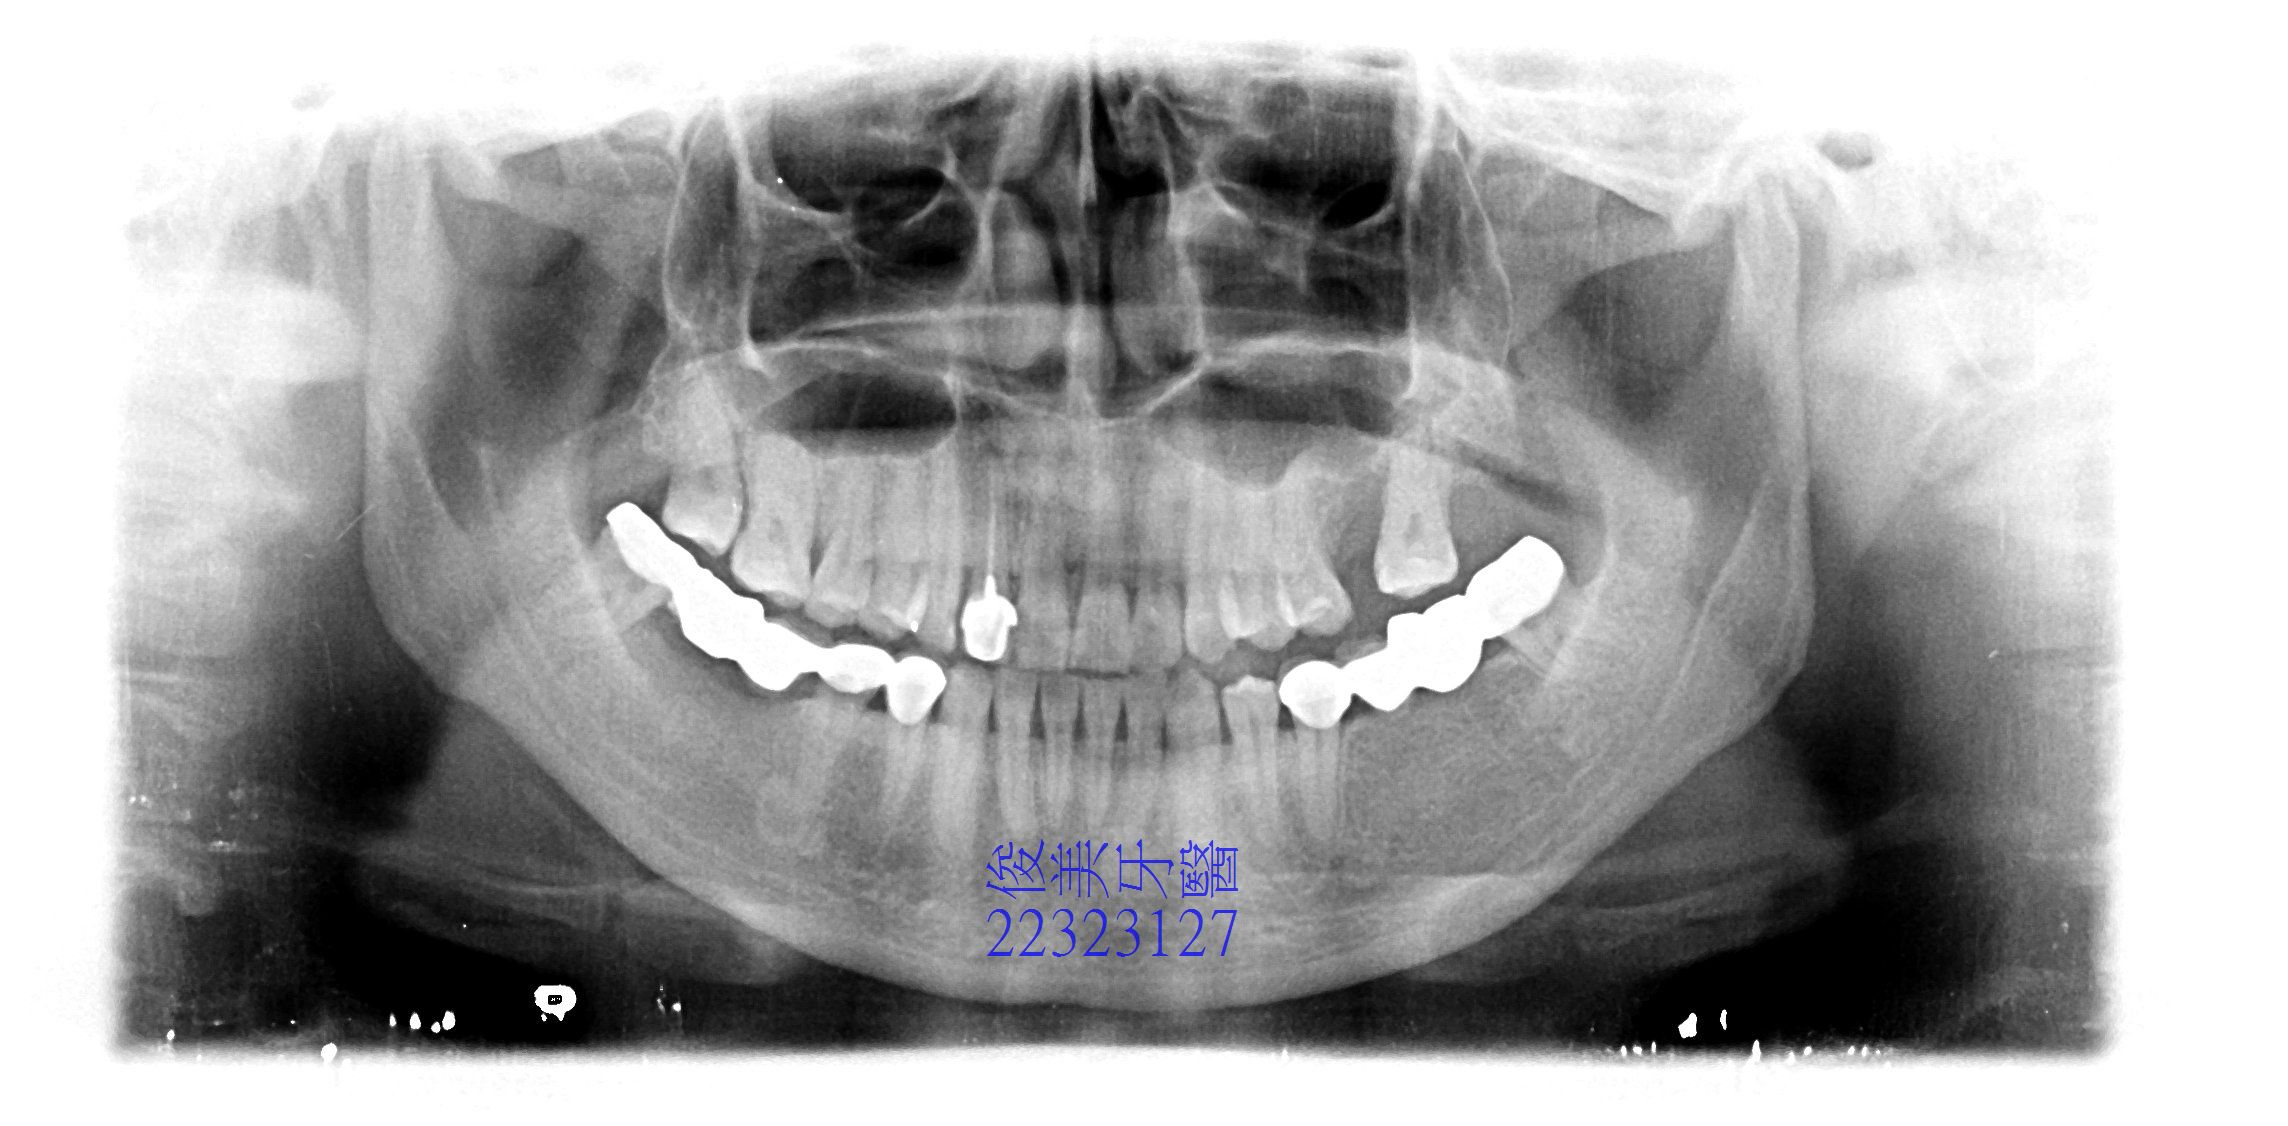

患者於門診中表示,想要做矯正治療, 將戽斗的咬合做改善,請醫師評估,醫師分析後給患者的建議為:

除需利用矯正來調整咬合外,下顎的智齒需拔除,缺牙也需修復,牙齒將來需利用全瓷整型貼片來修復形

態及大小,有些牙齒因長期不正確的方向受力,導致牙周破壞,患者也有不明頭痛的症狀,只能以服藥緩

解。

下排牙齒後牙因空間不足,採金屬牙修復,牙橋不易清潔。

因長期缺牙,側方骨頭皆已萎縮,牙脊過窄。需補骨。